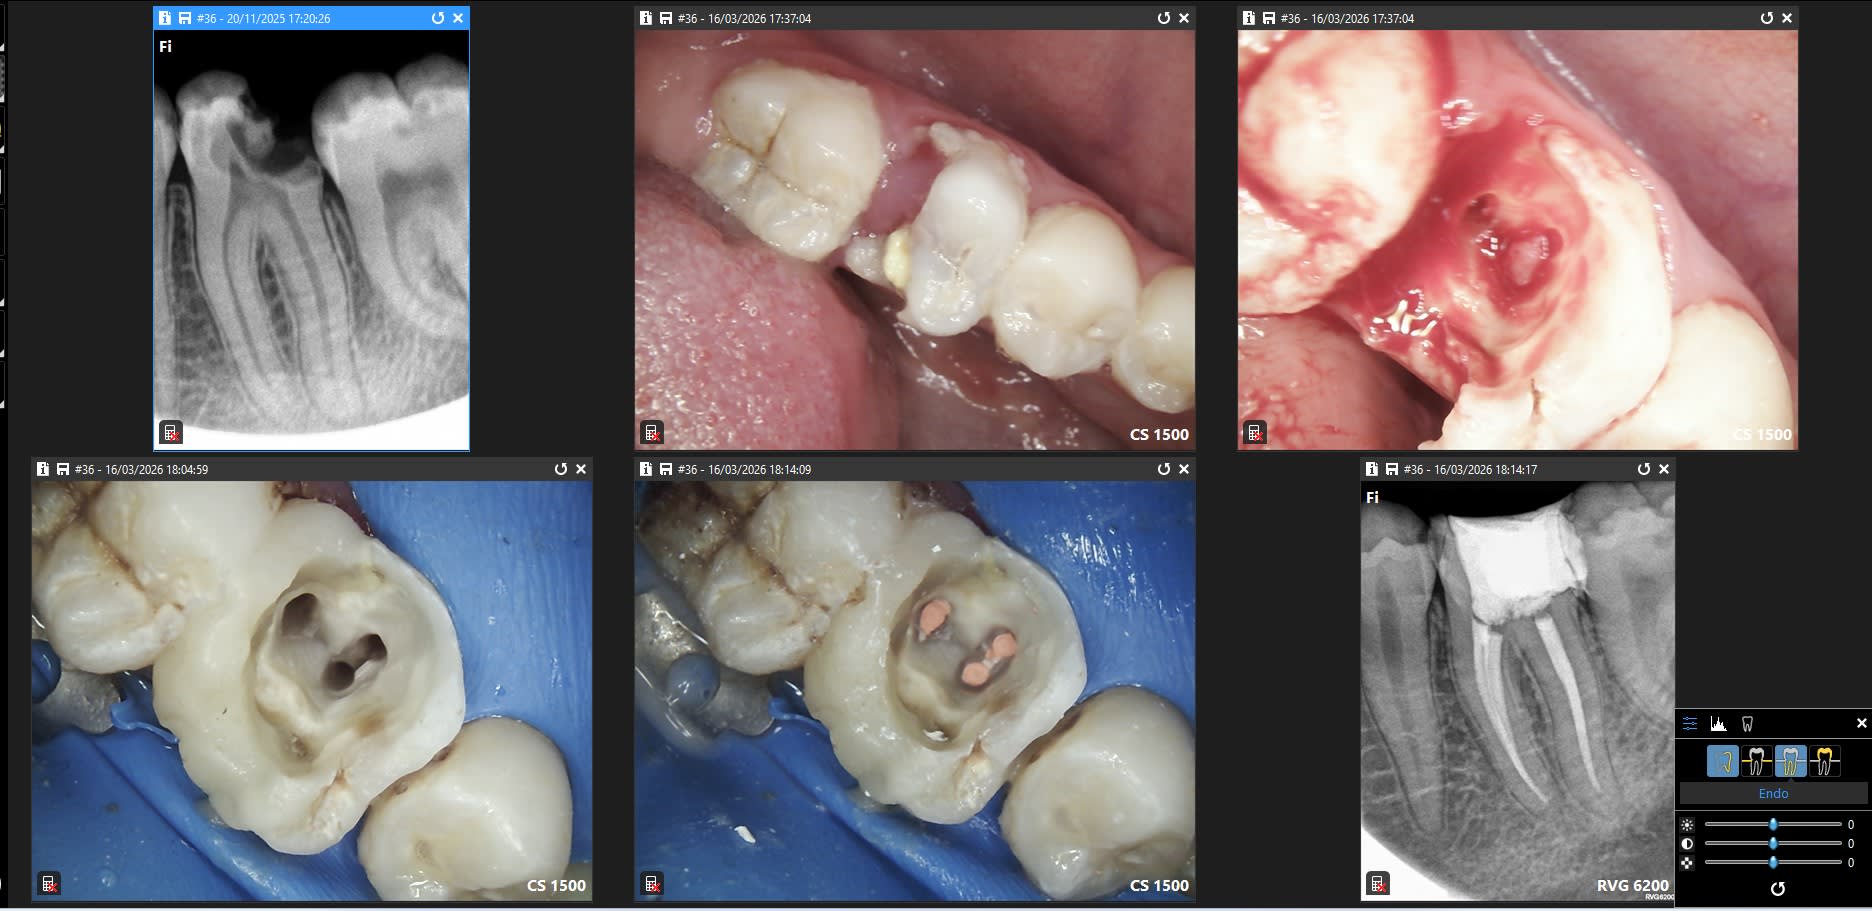

Toujours chiant une prémolaire à 3 canaux. C'est le genre de chose qu'il faut faire dans de bonnes conditions ( rcpe digue)

Belle réussite. Avec une racine distale aussi fine!!! Hors temps digue, c'etait long, chicot?

le mv2 est assez atypique ici...

le nombre de mv2 non traité doit quand même être assez important ...

Je les trouve pas à chaque fois en général ils sont sous un pont de dentine en position mésio linguale du mv1. Il faut creuser un peu mais t'as toujours un doute sur son existence et peur de faire une perfo en l'absence de cone beam.

Se mettre dans de bonnes conditions de travail. quelque soit la situation. Il n'y a plus de bagues de cuivre dommage.

46 last chance. Canaux mésiaux en Y : la bioceram remonte par l'autre canal.